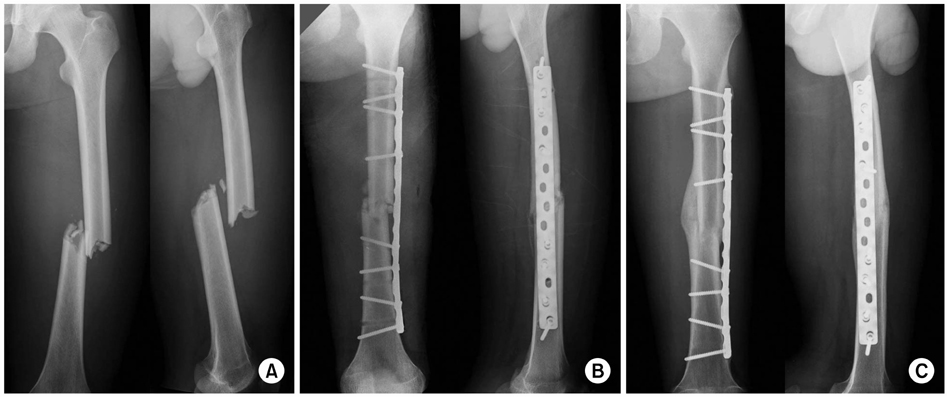

Shoebill,广嘴鹳属rex,大钩形的鸟,乌干达画象E 稀有人物以, jkfs-20-99-g007-l.jpg,